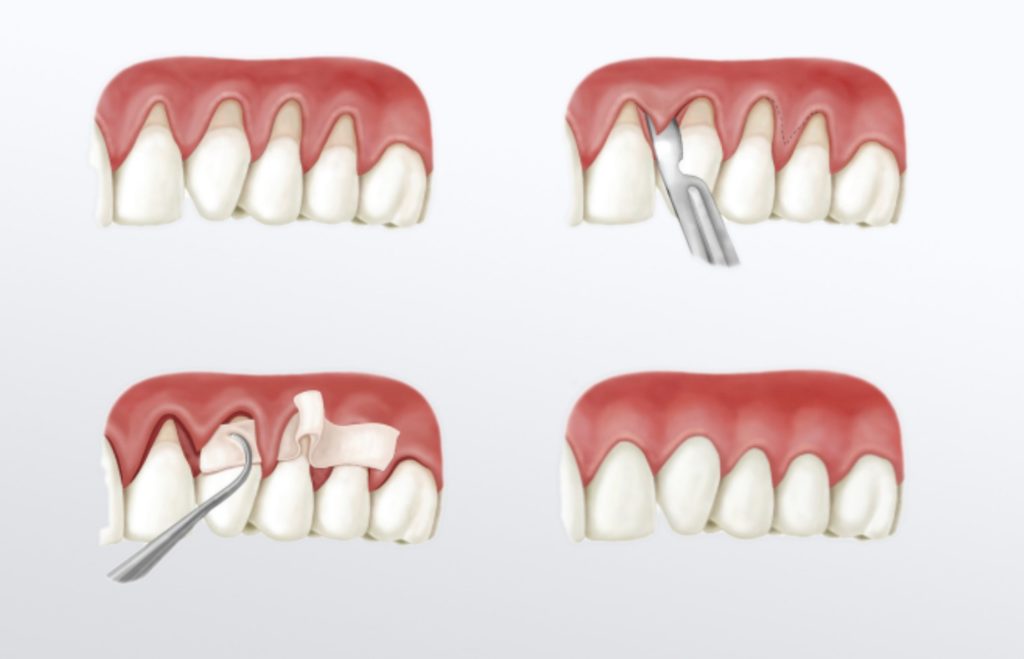

- enxertos gengivais;